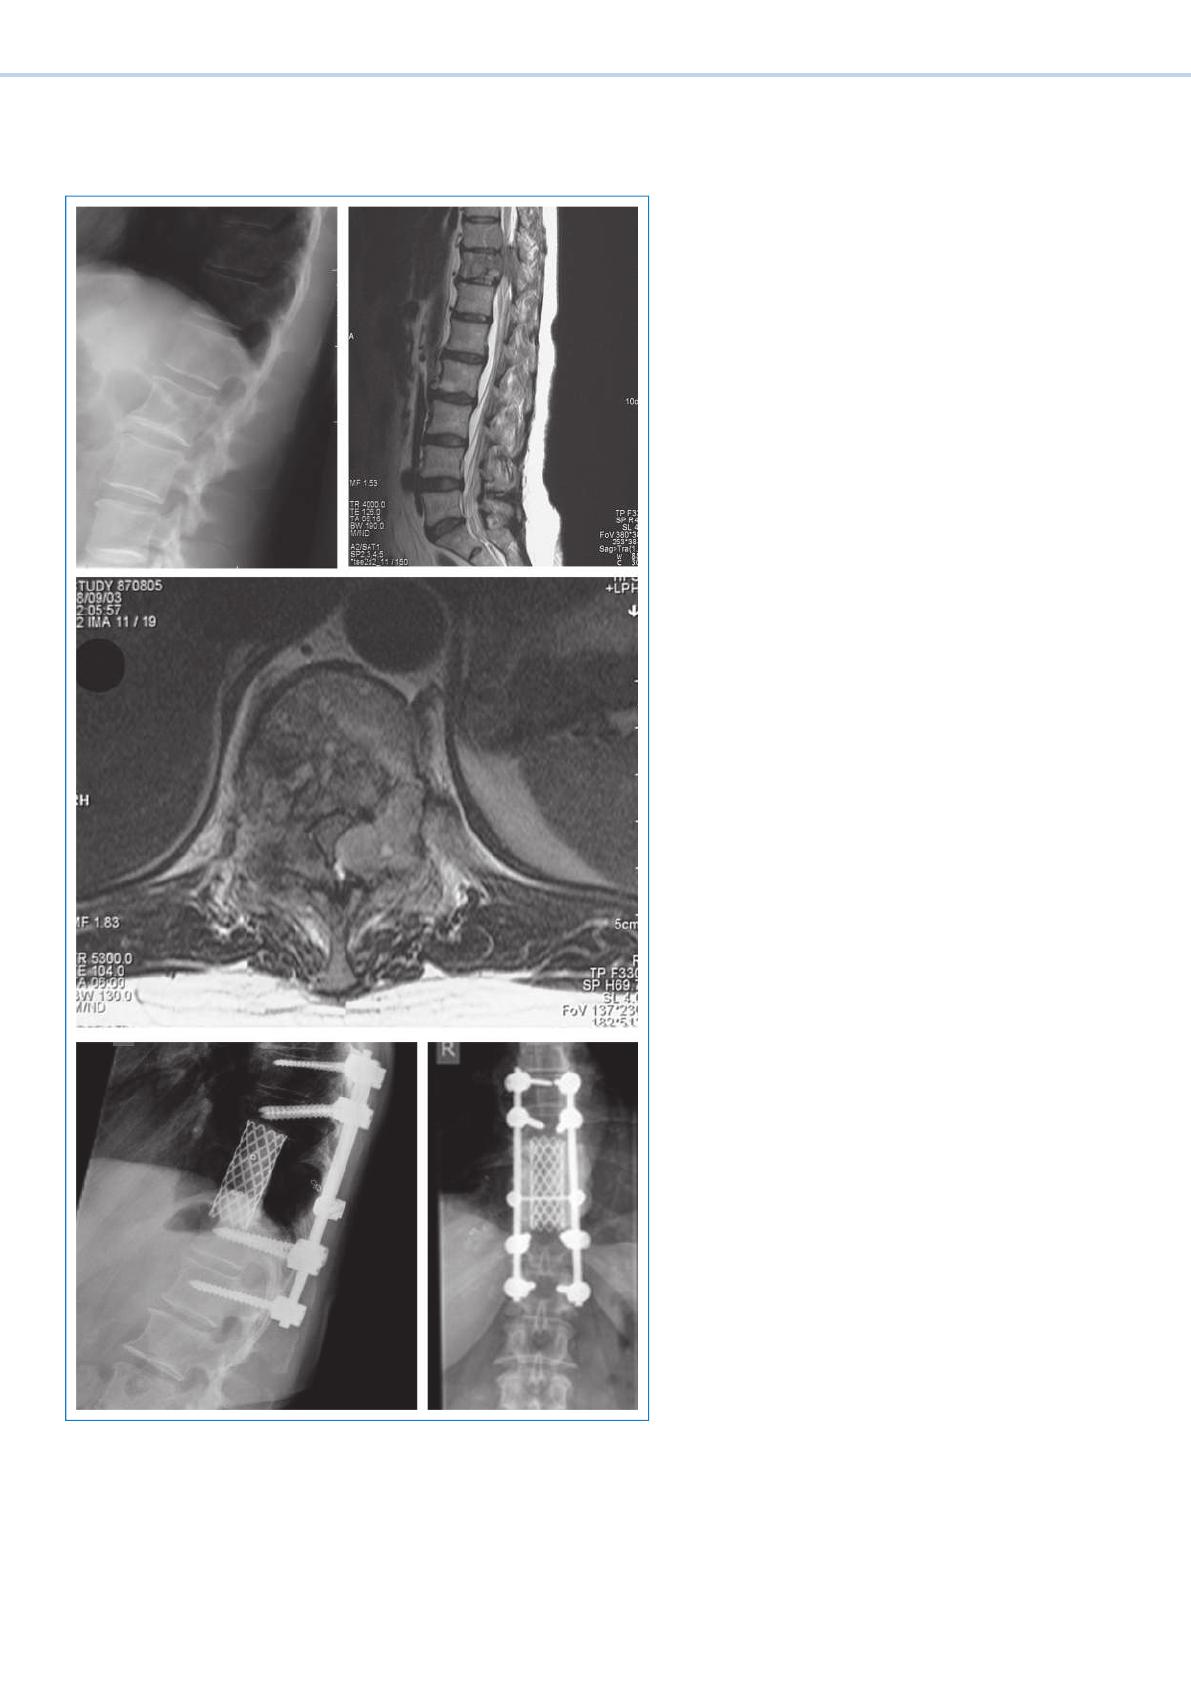

Tr aitement «state of the art»

de la compression spinale maligne

Tr aitement vertébrochirurgical de la compression

spinale maligne